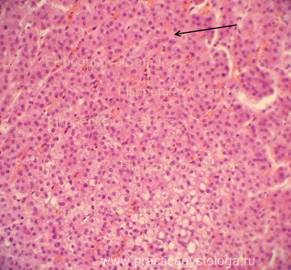

НАДПОЧЕЧНИК (1объект) - в срезах представлен преимущественно корковый слой надпочечника с преобладанием слабого его кровенаполнения. Строение коркового слоя не нарушено. Субтотальная выраженная делипидизация цитоплазмы адренокортикоцитов клубочковой и пучковой зон коры.

Рис. 3. Фрагмент коркового слоя надпочечника в состоянии слабого кровенаполнения. Субтотальная выраженная делипидизация цитоплазмы адренокортикоцитов клубочковой и пучковой зон коры. Окраска: гематоксилин и эозин. Увеличение х250.